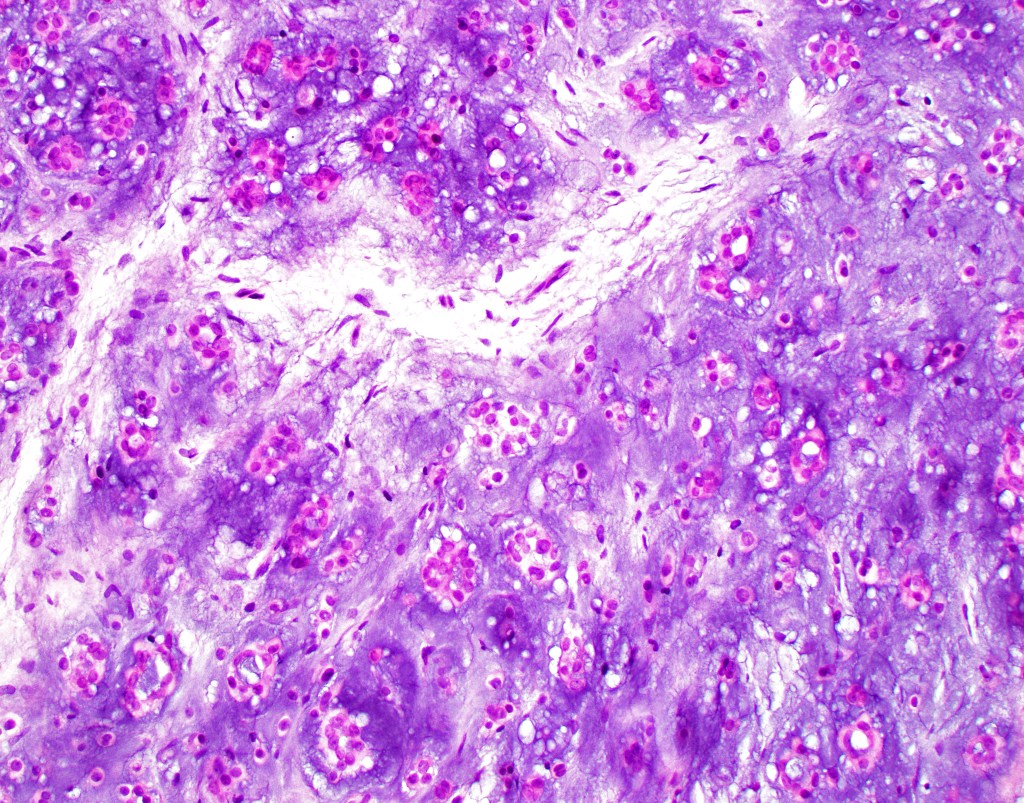

Histological features

•Infiltrative growth pattern

•Nuclear pleomorphism, prominent nucleoli

•Marked mitotic activity

•Abnormal mitoses

•Lymphovascular invasion

•Carcinosarcoma